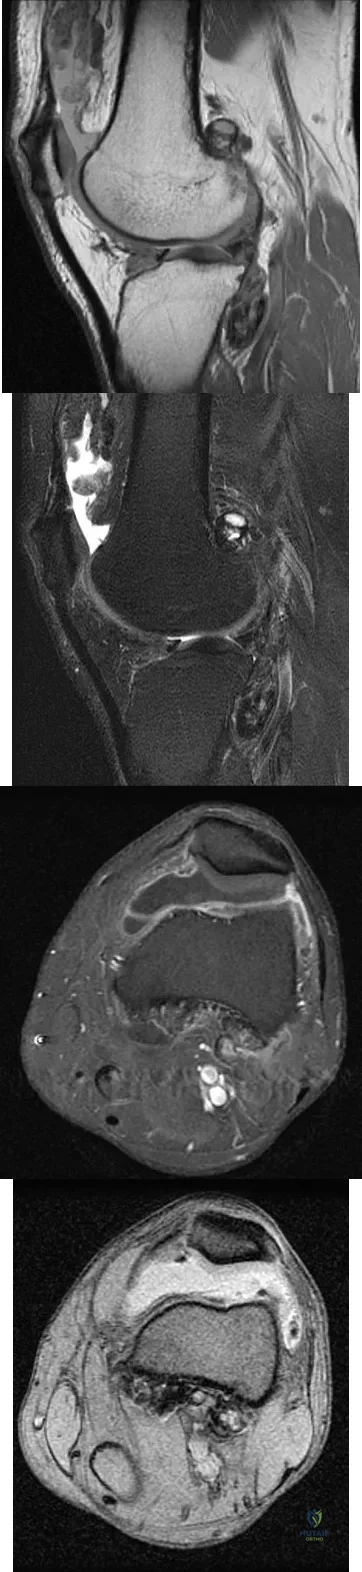

A 28-year-old man reports knee stiffness, swelling, and a constant ache that is worse with activity. Examination reveals an effusion, global tenderness, and warmth to the touch. Flexion is limited to 110 degrees. Figures 48a through 48d show sagittal T1-weighted, sagittal T2-weighted, axial T1-weighted fat-saturated gadolinium, and axial gradient echo MRI scans. Based on these findings, what is the most likely diagnosis?

Explanation